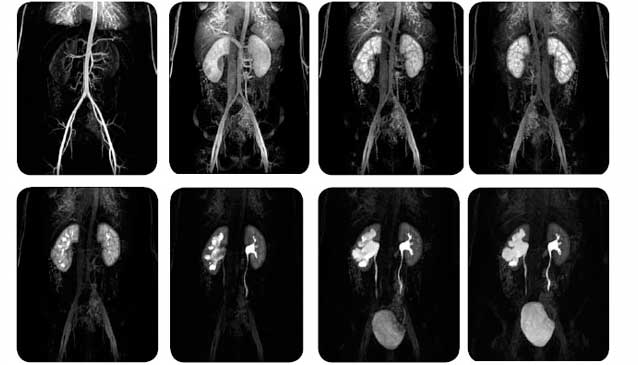

La urografía es un examen radiográfico de contraste, que consiste en la realización de radiografías seriadas para ilustrar el paso de contraste previamente administrado por vía intravenosa.1 El contraste permite la exploración y el estudio de diversas secciones de las vías urinarias y detectar alteraciones en la secreción urinaria, desde el parénquima renal hasta la vejiga.

El estudio se basa en visualizar la excreción renal con el paso de los medios de contraste yodados que logran oscurecer la orina y, por tanto, hacer visibles las cavidades naturales de las vías urinarias: los conductos colectores del riñón, uréter y vejiga urinaria. La urografía permite la exploración morfológica y funcional de estos .

Morfología, ya que proporciona una imagen fiel de los riñones y de la vía excretora; Funcional, ya que ofrece información precisa sobre la depuración de los riñones.

Después de inyectar un medio de contraste a base de yodo en la vena, la urografía permite ver y estudiar las diferentes secciones del tránsito de excreción de la orina: cálices y ampolla renales, los uréteres y la vejiga.1 De cada una de estas secciones se evaluará el tipo, la ubicación, el tamaño, el curso (en el caso de los uréteres) y la apriencia de las paredes tubulares.

Además de estos hallazgos morfológicos, se pueden demostrar hallazgos funcionales, tales como apariencia, la durabilidad y la simetría de la eliminación, la intensidad y homogeneidad de la opacidad y la motilidad de las diversas secciones (la pelvis renal, uréteres y vejiga). Todos estos datos permiten una evaluación precisa de la función renal y las diversas secciones de la excreción. La urografía es el examen de primera elección en todas las enfermedades de las vías urinarias, tales como